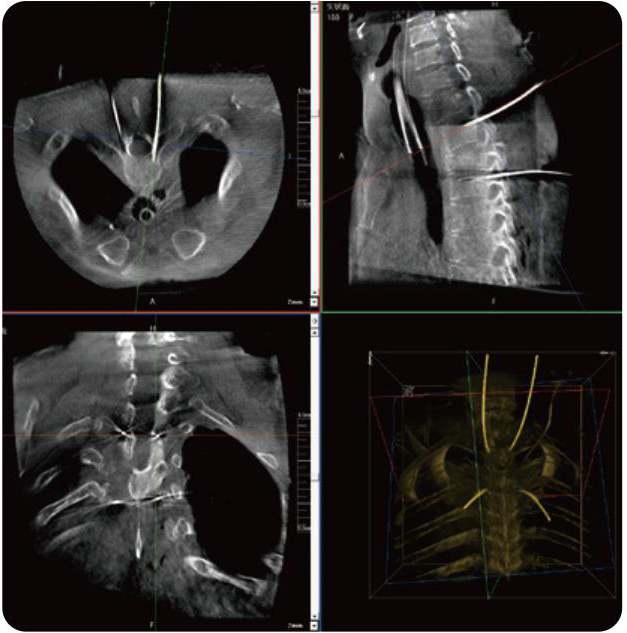

PL300B可應(yīng)用于多節(jié)段脊柱外科手術(shù),輔助醫(yī)生定位病灶部位,為脊柱外科手術(shù)(經(jīng)皮椎體成形術(shù)、椎弓根螺釘內(nèi)固定術(shù)等術(shù)式)提供術(shù)前手術(shù)流程規(guī)劃、入釘位置、角度可視化引導(dǎo),模擬仿真入釘輔助。

PL300B搭配普愛醫(yī)療自主研發(fā)生產(chǎn)的平板3D C形臂,借助一體化自適應(yīng)配準(zhǔn)( 軌跡配準(zhǔn))技術(shù),通過追蹤C形臂三維采集軌跡,自動完成圖像坐標(biāo)建立和系統(tǒng)坐標(biāo)配準(zhǔn)。配準(zhǔn)精度更高,操作步驟少,系統(tǒng)運作效率高。